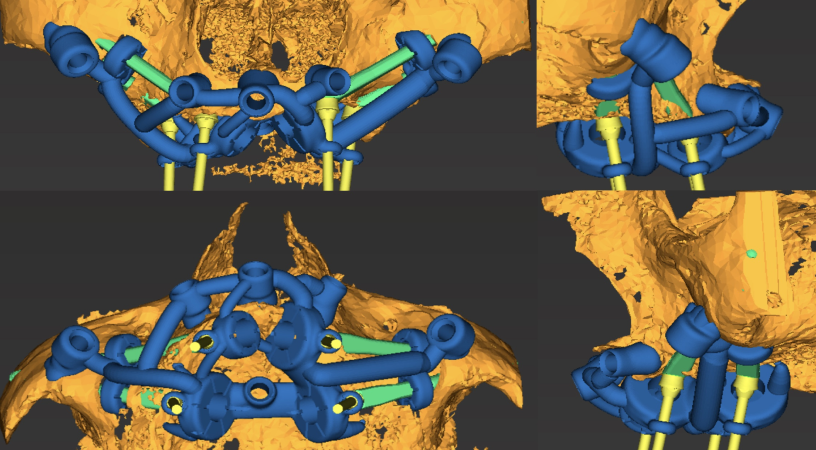

L’étude implantaire se fait à l’aide d’un logiciel de planification qui intègre le design de la future prothèse qui a été validé d’un point de vue esthétique et fonctionnel pour optimiser le placement des implants. Une fois validé un guide chirurgical en titane imprimé monobloc, est conçu pour reproduire lors de la chirurgie la position virtuelle des implants planifiés gage de plus de précision et de sécurité chirurgicale. C’est un guide à double douille qui stabilise le foret lors du passage dans le maxillaire puis dans le zygoma. L’extension zygomatique du guide est retirée après le forage pour laisser passer l’implant zygomatique guidé.